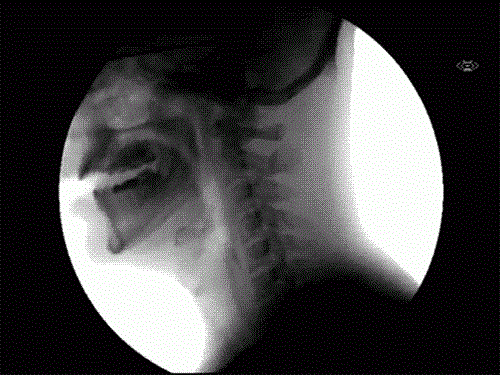

39. Dies ist eine Röntgenaufnahme eines Hundes, der Wasser trinkt.